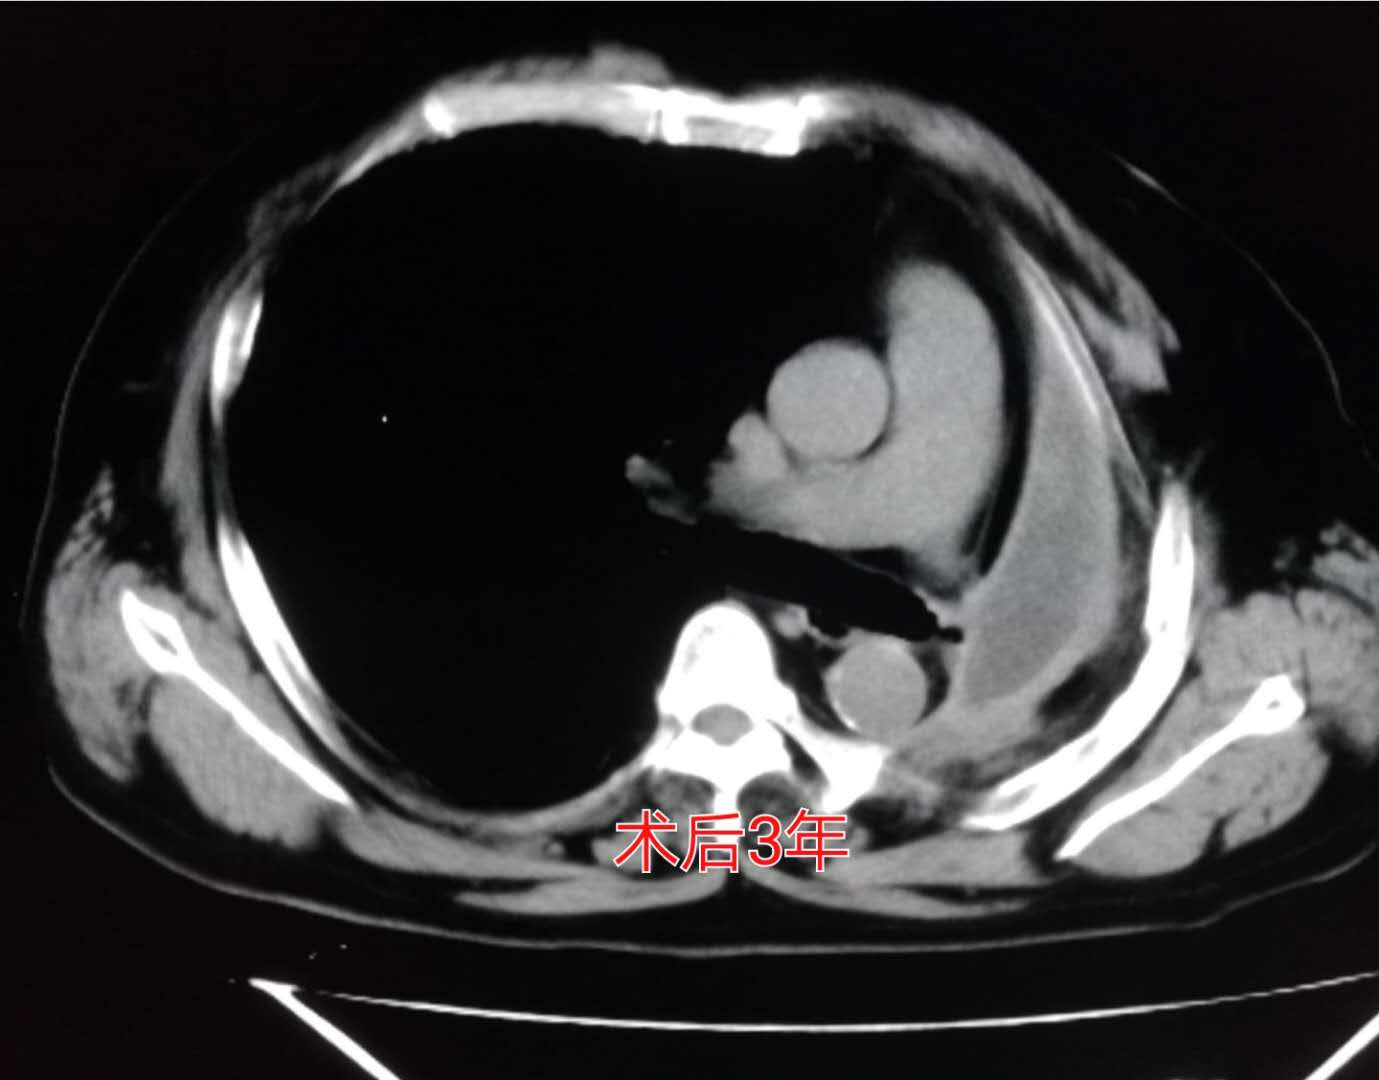

这位老爷子的家属全面考虑后选择冒险赌一把,做了左侧全肺切除。

手术很成功!

术后第3年复查的时候:

我们可以看到左侧胸腔形成了术后残腔。